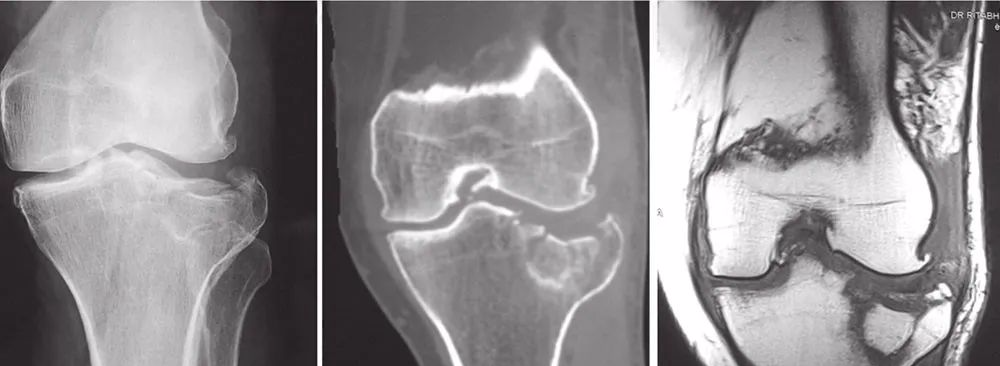

影像

图2 X线片,CT, MRI资料

X线片对于急诊诊断骨折很有帮助。然而,关节内的病理解剖用CT来划定更合适。冠状面上粉碎性骨折中关节内损伤、塌陷以及骨折解剖的程度在CT扫描上更为形象。如果怀疑有半月板和韧带损伤,可以用MRI进行评价(图2)。

图18 术前CT扫描

图19 A和B冠状位CT图像显示后部的粉碎(A),前柱完整(B)

图20 A和B矢状位显示冠状的骨折线位于中间(A)和外侧(B)

27岁男性患者,在交通意外中受伤。他从自行车上跌落,诉左膝严重疼痛,伤后无法站立。这是个单独的损伤。X线片(图17)和CT(图18~图20)显示左胫骨平台双髁骨折。用两块内固定钢板进行开放复位和内固定(图21)。患者术后1年,影像学表现良好(图22),临床功能(图23)恢复良好。